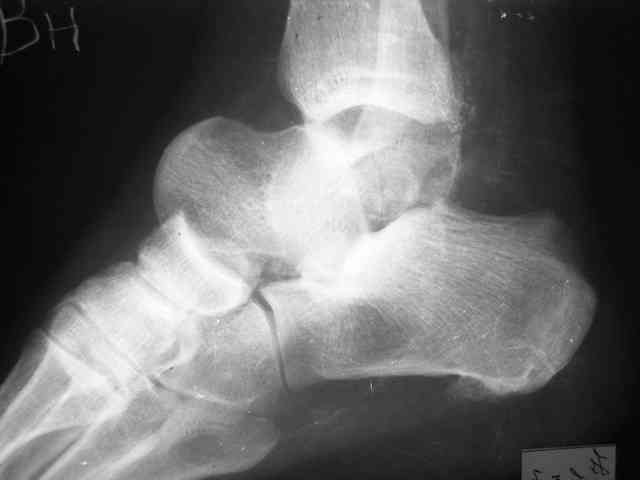

Уважаемый Александр! Как обещал представляю Р-граммы и операционные фото.

Можно убрать таранную кость, и поместить в образовавшуюся полость либо бусы из цемента с антибиотиками, либо вылепленный прямо по форме тарана спейсер. Целесообразность этого будет определяться распространенностью гнойного процесса. Может быть, будет достаточно только удаления тарана.

Вместе с аваскулярным куском кости устранится субстрат. Надо опасаться не мягких тканей, а плохо кровоснабжаемых. Если после удаления тарана добиться контакта хорошо васкуляризованных пятки и больщшеберцовой, мягкие ткани не давить, чтобы некроза раны не было, то все должно зажить.